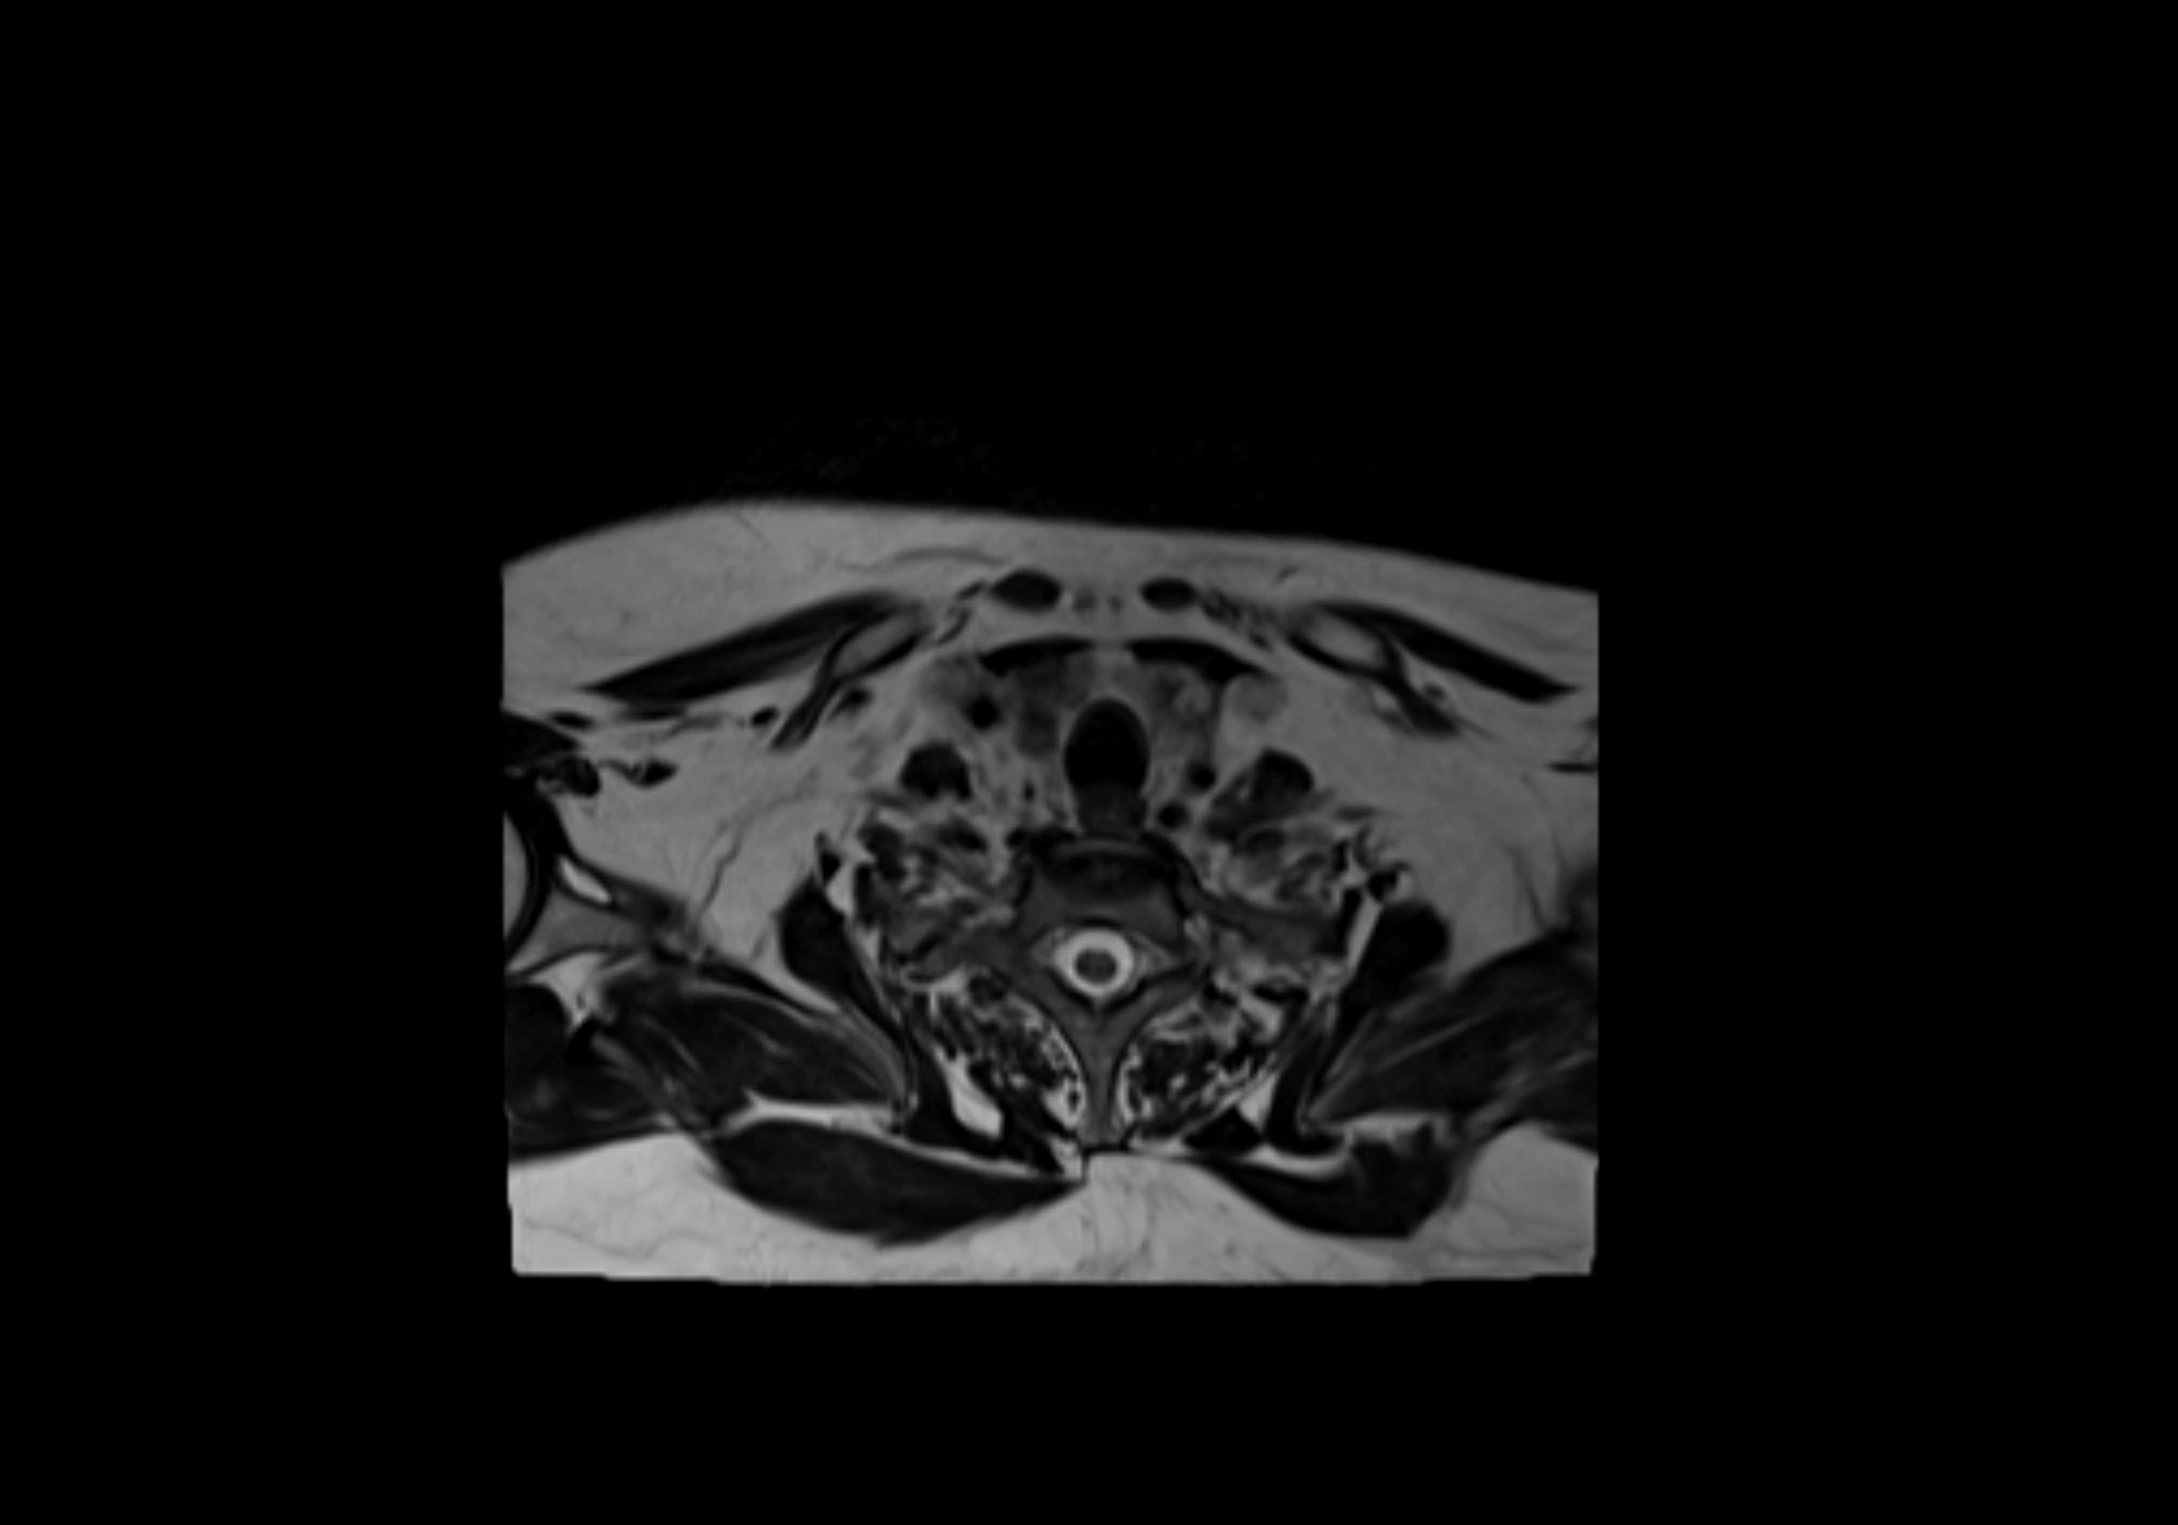

MRI Appearance

T1-weighted images:

• Normal accessory nodes appear as small, oval hypointense to intermediate signal structures within subcutaneous fat

• Surrounded by hyperintense fat, enhancing contrast for visualization

T2-weighted images:

• Nodes show intermediate signal, with surrounding fat bright

• Useful for detecting edema, inflammation, or infiltration

• Fatty hilum may appear slightly hyperintense relative to cortex

MRI images

image